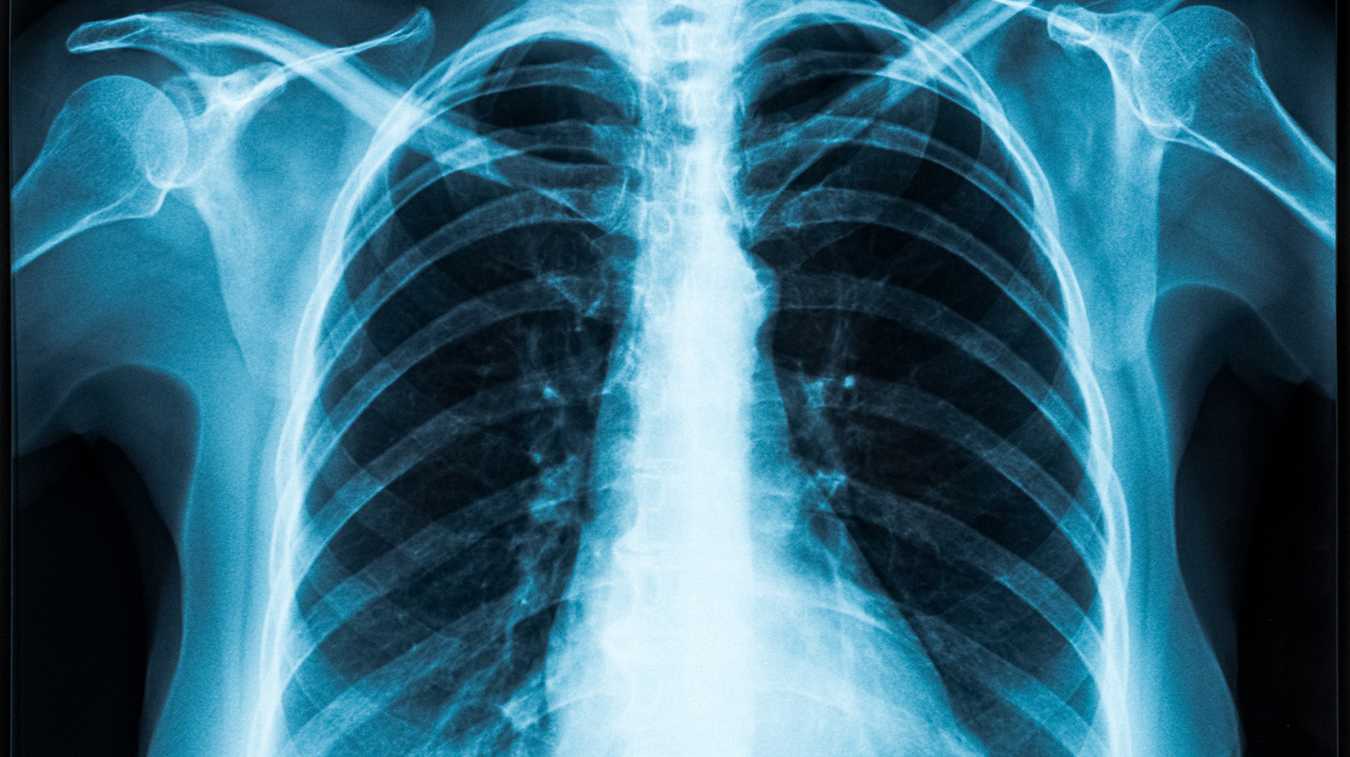

La enfermedad pulmonar por radiación es consecuencia de la radioterapia administrada en la región del tórax para tratar el cáncer de pulmón, de mediastino, de mama o un linfoma. La radioterapia provoca un efecto biológico en las células sanas y neoplásicas por lo que el daño pulmonar siempre está presente; sin embargo, su magnitud depende de factores del paciente y del esquema radioterápico.

La lesión pulmonar inducida por radioterapia (LPIR) comprende dos fases: una fase temprana conocida como neumonitis por radiación (NR), caracterizada por inflamación aguda del tejido pulmonar como resultado de la exposición a la radiación; y una fase tardía llamada fibrosis por radiación (FR), un síndrome clínico que resulta del daño crónico del tejido pulmonar.